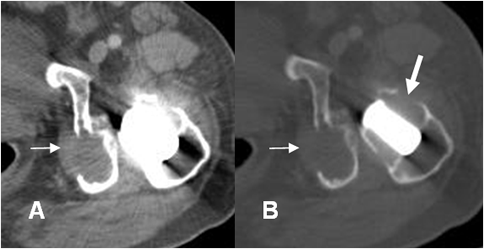

Fig 126 E. Granulomatosis agresiva.

A: RM coronal en T1, B: RM coronal en T2 y C: RM coronal en STIR. Igual paciente anterior. Artefactos metálicos producidos por la prótesis, la cual está rodeada por líquido. En el trocánter mayor hay zona de fibrosis, hipointensa en todas las secuencias.